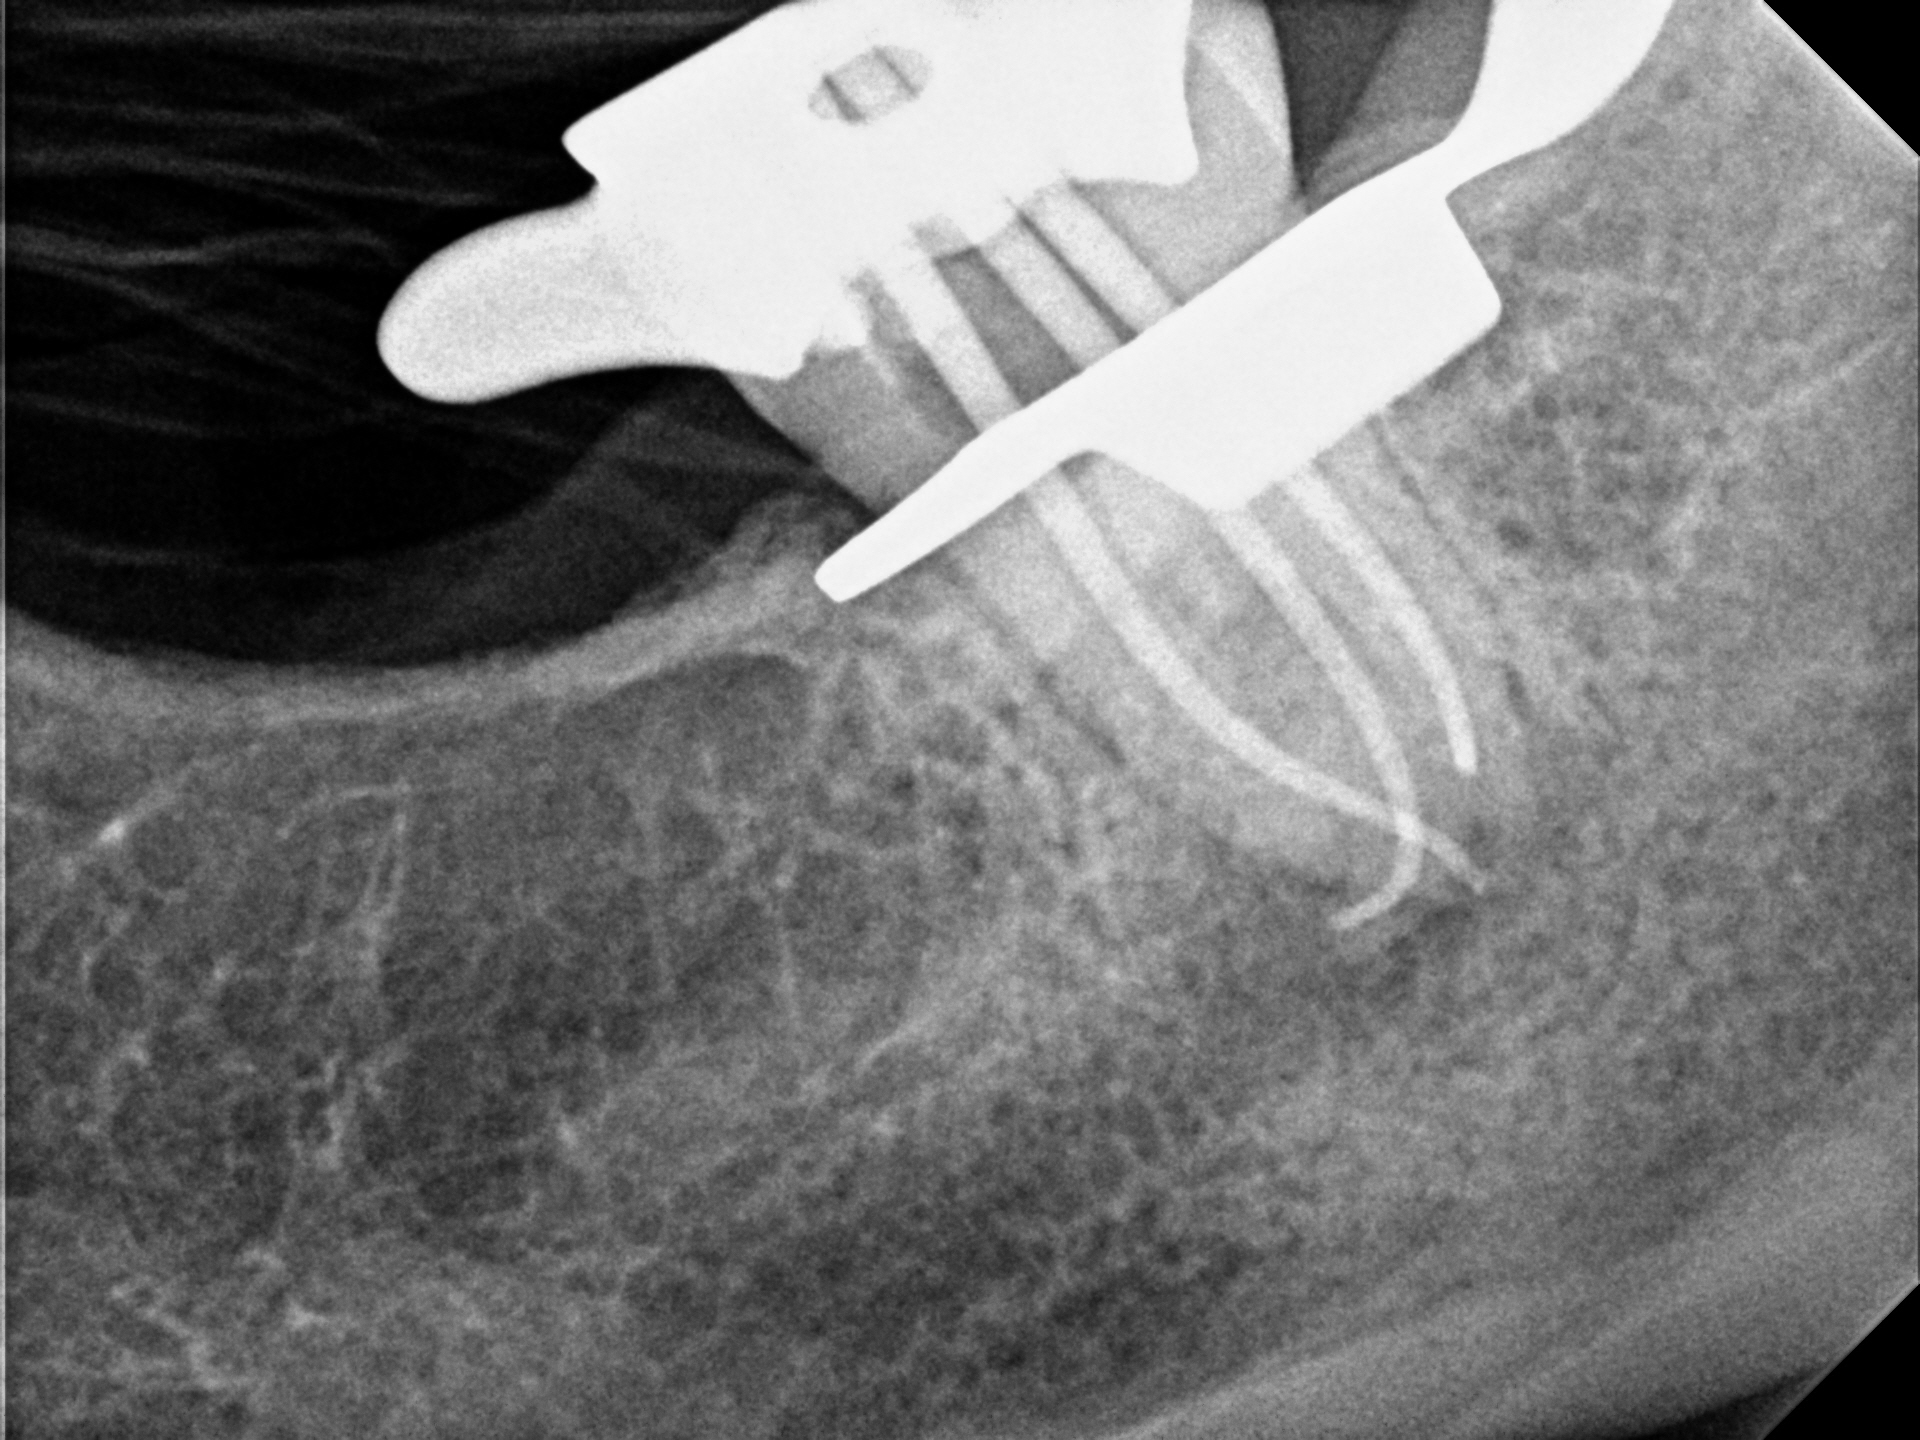

1_Case7 PreOp1 11-24-2014

11_Case7 PostOp1 12-11-2014

14_Case7 Recall2 9-27-2016

Case 14

An example of a root end surgery (apicoectomy). The tooth had a prior root canal treatment and an instrument broke inside the root. There was also resorption (dissolving) of the root tip by the infection. The broken file blocks treatment in the canal space, so I surgically removed the portions of the root with the instrument and also the portion of the other root with the resorption. The ends of the roots were cleaned and filled. The final X-ray, taken two years later, shows perfect healing.